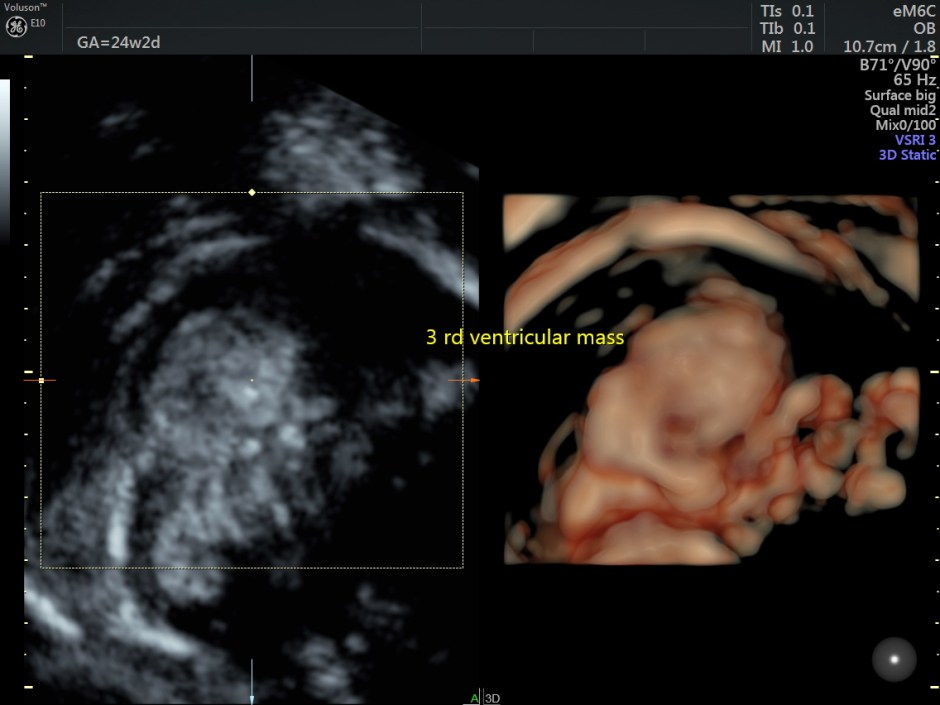

A careful look at the 3rd ventricle shows a solid mass.

Some reconstructed images are given below.

Choroid plexus papilloma (CPP) is a rare and benign tumor composed of epithelial cells that line the ventricular choroid plexus and correspond to 0.4%-0.6% of fetal intracranial tumors. CPP may develop in the lateral ventricle, third ventricle, and fourth ventricle. It is generally diagnosed during the third trimester and is always associated with unilateral or bilateral ventriculomegaly. CPP has slow growth and noninvasive behavior; however, because of its specific location, CPP can block the drainage of cerebrospinal fluid and cause hydrocephalus.

An echogenic mass involving the choroid plexus is visualized on US and MRI. Color Doppler imaging may be useful to show vascularization in the lesion.